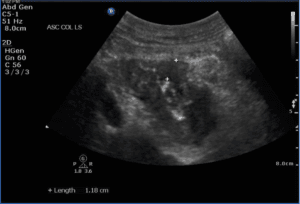

Two days later, the patient returned with worsening abdominal pain, diarrhea, and vomiting. Her vital signs were within normal limits and her abdominal exam was unchanged. A repeat POCUS was performed which revealed free intraabdominal fluid, dilated loops of small bowel (Figure 2a, b), evidence of hyperechoic foci within the bowel wall (Figure 2b), and a-lines within the abdomen concerning for pneumatosis (Figure 2c).

Figure 2. (a): A point of care ultrasound (POCUS) image of the abdomen with a curvilinear probe showing a dilated loop of small bowel (arrow) with free fluid (dashed arrow), and a visualization of the bladder (star). (b): A point of care ultrasound (POCUS) image of the abdomen showing dilated loops of small bowel with evidence of hyperechoic foci within the bowel wall (arrow) and the presence of free intra-abdominal fluid (star). (c): A point of care ultrasound (POCUS) image of the right upper quadrant in sagittal orientation showing a-lines within the abdomen (arrow) with reverberation artifact.